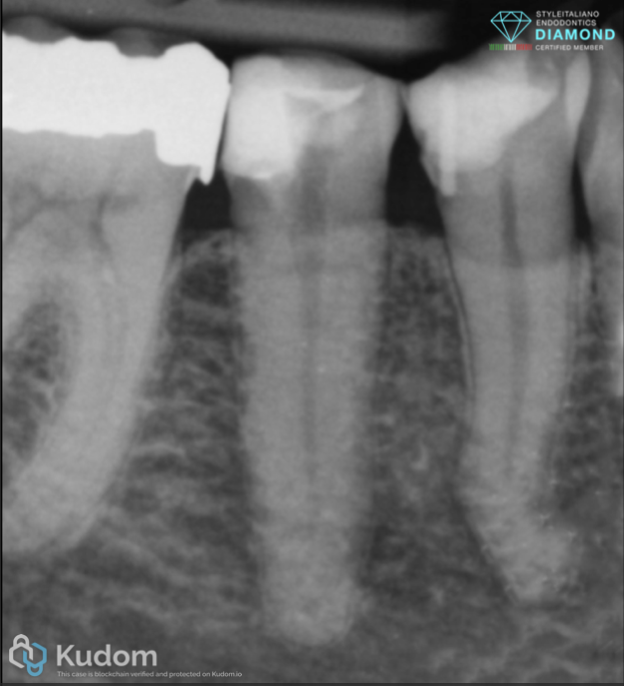

Fig. 1

A patient presented with a symptomatic mandibular second premolar requiring endodontic treatment. Post-endodontic evaluation revealed significant loss of dental tissue, with wall thickness deemed insufficient to support a direct restoration without reinforcement. Radiographic and clinical probing confirmed a markedly oval cross-section of the canal orifice.